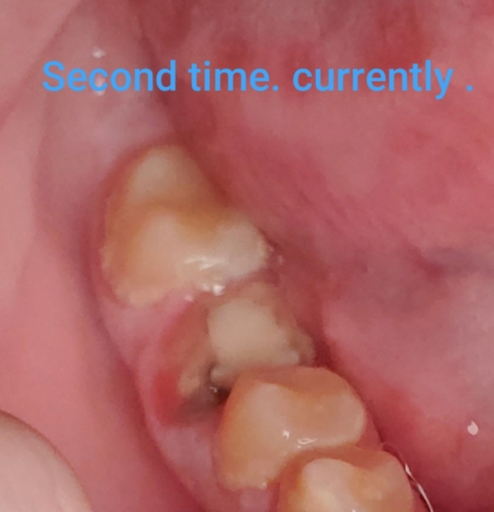

Hi . My crown fell off my root canal . I had the root canal done a little over a month ago . A week later the crown fell off . I went back and they put a new crown on . But now it fell off . The root canal tooth also seems to hurt in a way . Its red...